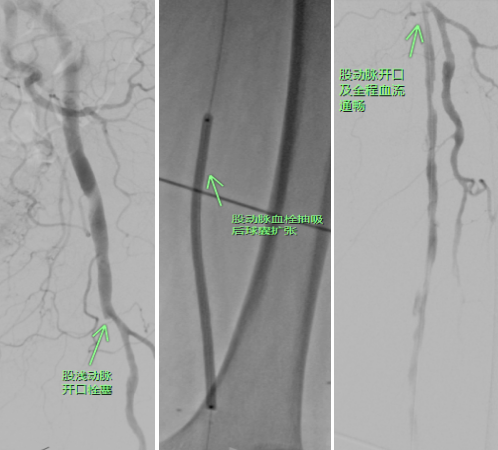

面对病情快速进展的严峻形势,副主任陈健、杨小进当机立断,决定立即实施手术。当天夜间,医护团队紧急为徐奶奶进行了经皮股动脉血栓抽吸术+股动脉球囊血管成形术+腘动脉造影+腘动脉球囊血管成形术+胫动脉球囊血管成形术+股动脉造影术+髂动脉造影术。

术前(左),术后(右)

术后,徐奶奶左下肢循环立即得到显著改善,皮肤大面积的紫红色消退,疼痛也明显缓解。目前,徐奶奶生命体征平稳,正在康复中。徐奶奶及其家属对医护团队精湛的医术和悉心的照护表达了万分的感谢。